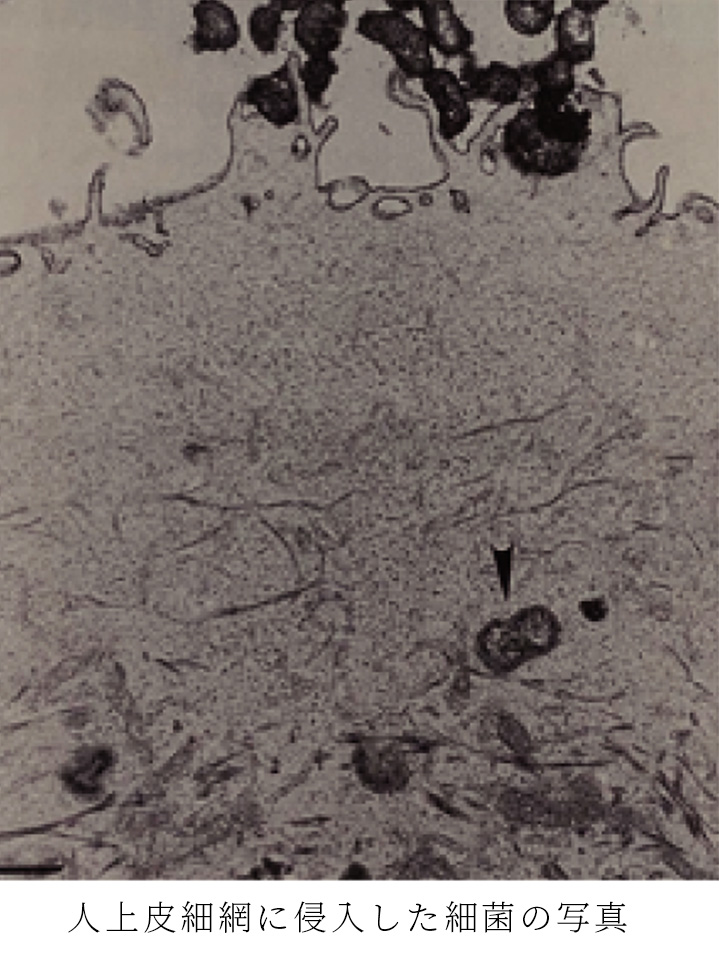

歯周病菌は歯石の中にいると考えられ、“歯周治療は歯石を取れば良い”とされてきましたが、最新の研究で歯周病菌は歯周ポケットの上皮細胞内に侵入しており、歯周病菌の除去には歯石除去に加え歯周ポケット上皮を歯周病菌ごと剥がし取る必要があることがわかりました。これを可能にするのがスウェーデン・イエデボリ大学で開発された「ペリオプロ」治療。殺菌力は「クロルヘキシジン」の倍以上あり、歯石除去後の歯肉の再付着を容易にします。保険診療で治療が長引いている方、また痛いことが嫌いで「麻酔をして歯石除去を何度もやるのは嫌!」という方にもおすすめです。